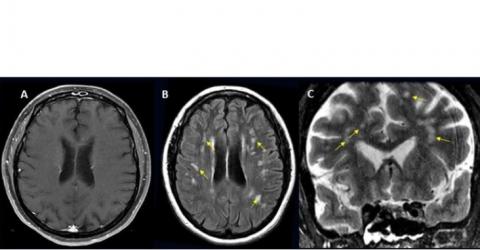

- chez les patients hospitalisés ayant besoin de subir une IRM ou une tomodensitométrie (CT-scan) du cerveau, l'examen s’avère positif (diagnostic d’un problème cérébral) environ 10 % du temps ;

- les complications les plus fréquentes comprennent l'accident vasculaire cérébral ischémique (AIT), avec une incidence de 6,2 %, suivi par l'hémorragie intracrânienne (3,72 %) et l'encéphalite (inflammation du cerveau) (0,47 %) ;

- certaines complications cérébrales rares sont également identifiées telles que l'encéphalomyélite aiguë disséminée (ADEM), une inflammation du cerveau et de la moelle épinière et le syndrome d'encéphalopathie postérieure réversible (SEPR), un syndrome qui induit de nombreux symptômes similaires à ceux de l’AVC ;